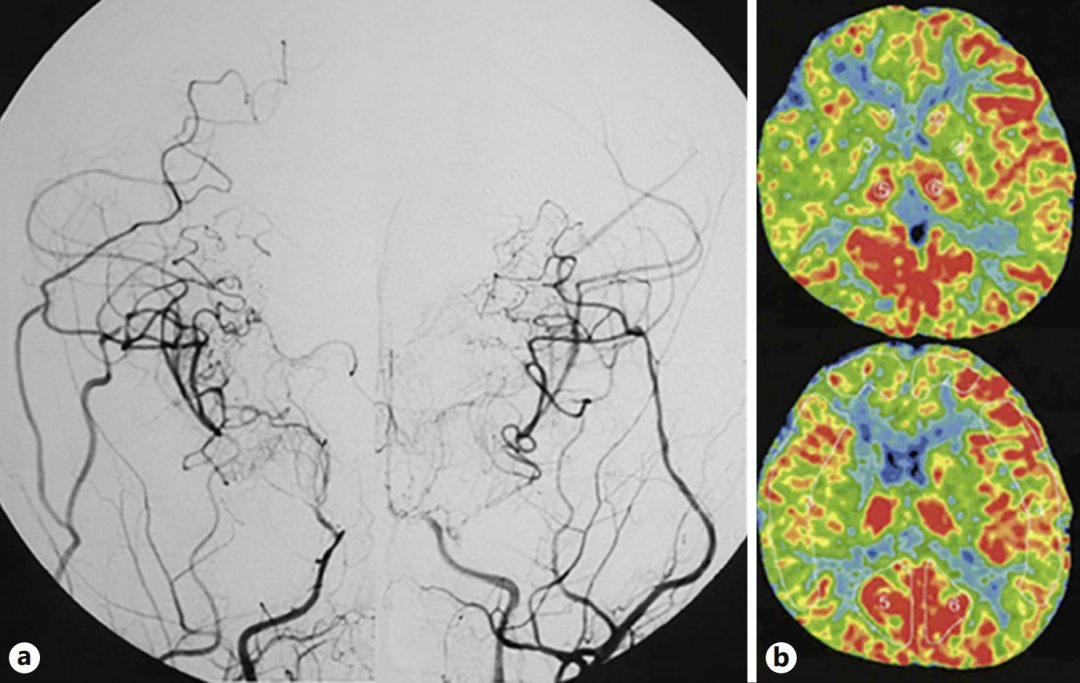

图a:第二次手术半年后,双侧颈内动脉血管造影显示侧支血管网络发育良好,基底烟雾血管消退。图b:双侧脑血流显示有所改善。